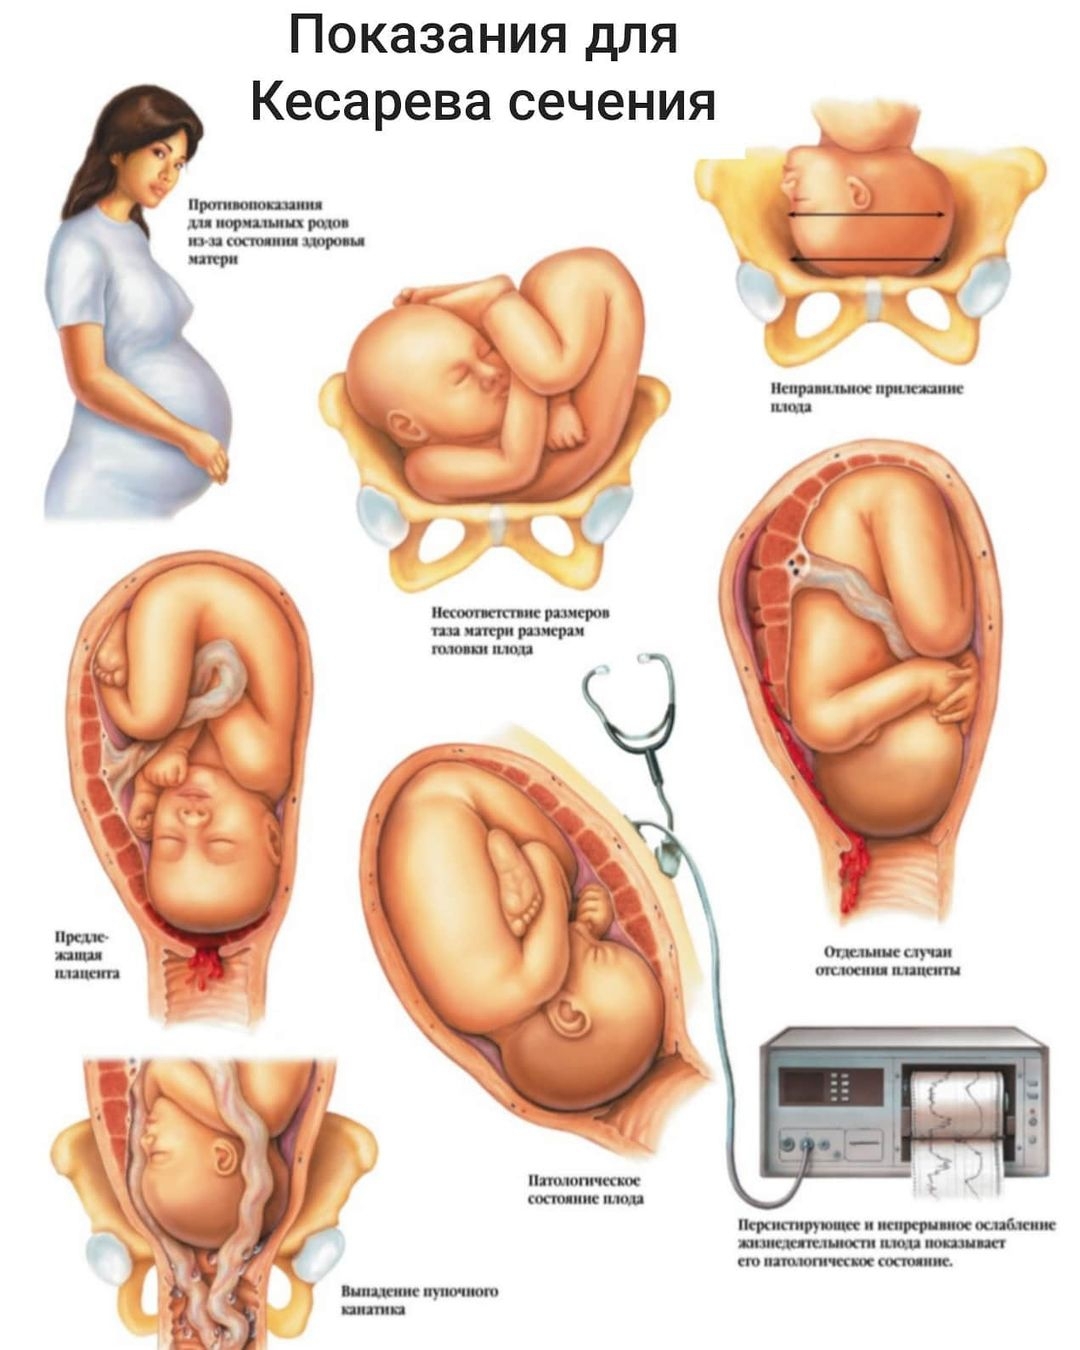

Показания к кесареву сечению